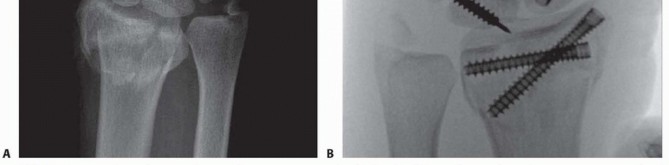

### TECH FIG 3 • A. The PA radiograph shows a displaced fracture of the radial styloid. B. This lateral radiograph shows metaphyseal comminution associated with the displaced radial styloid fragment. Because of the metaphyseal comminution, it was decided to stabilize the fracture using a volar plate.

* Open Reduction and Stabilization Perform a standard volar approach, and do not open the radiocarpal joint capsule ( TECH FIG 4A). The radial styloid fragment and the volar ulnar fragment are reduced to the shaft under direct visualization. The radial styloid fragment is provisionally pinned.*